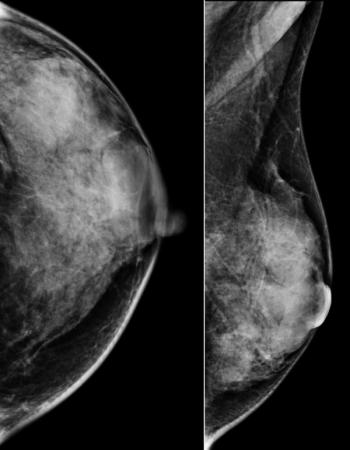

A 46-year-old patient presented for a second opinion on a mass found within the right breast on a prior outside mammogram. The patient denies any lumps or pain within either breast.